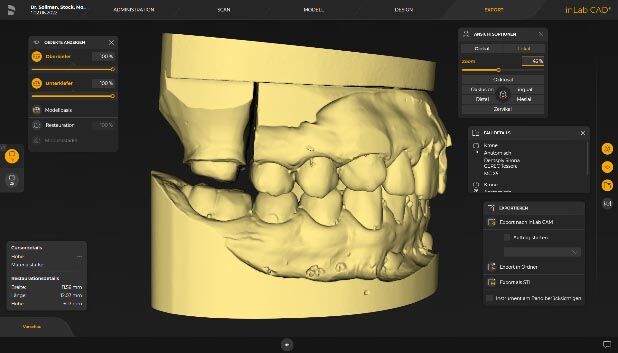

Lateral view of the digitally articulated models. Occlusal relation at tooth 16.

Lateral view of the digitally articulated models. Occlusal relation at tooth 26.